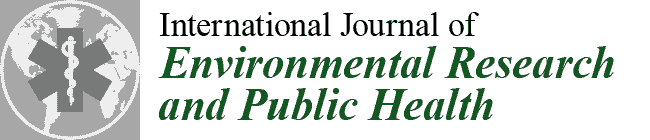

2.4. Evaluating the Therapeutic Response

2.6.1. Analysis of the Wong–Baker Pain Rating Scale Pain Scores

- Karcioglu, O.; Topacoglu, H.; Dikme, O.; Dikme, O. A systematic review of the pain scales in adults: Which to use? Am. J. Emerg. Med. 2018, 36, 707–714. [Google Scholar] [CrossRef]

- Rocha, M.O.C.; Cruz, A.A.C.F.; Santos, D.O.; Douglas-De-Oliveira, D.W.; Flecha, O.D.; Gonçalves, P.F. Sensitivity and specificity of assessment scales of dentin hypersensitivity—An accuracy study. Braz. Oral Res. 2020, 34, e043. [Google Scholar] [CrossRef]

- Alghadir, A.H.; Anwer, S.; Iqbal, A.; Iqbal, Z.A. Test-retest reliability, validity, and minimum detectable change of visual analog, numerical rating and verbal rating scales for measurement of osteoarthritic knee pain. J. Pain Res. 2018, 11, 851–856. [Google Scholar] [CrossRef] [PubMed] [Green Version]

- Marilyn, J.H.; David, W. (Eds.) Pain Assessment and Management. In Wong’s Nursing Care of Infants and Children, 10th ed.; Mosby: Maryland Heights, MO, USA, 2015; Chapter 5; ISBN 9780323222419. [Google Scholar]

- Adeboye, A.; Hart, R.; Senapathi, S.H.; Ali, N.; Holman, L.; Thomas, H.W. Assessment of Functional Pain Score by Comparing to Traditional Pain Scores. Cureus 2021, 13, e16847. [Google Scholar] [CrossRef] [PubMed]